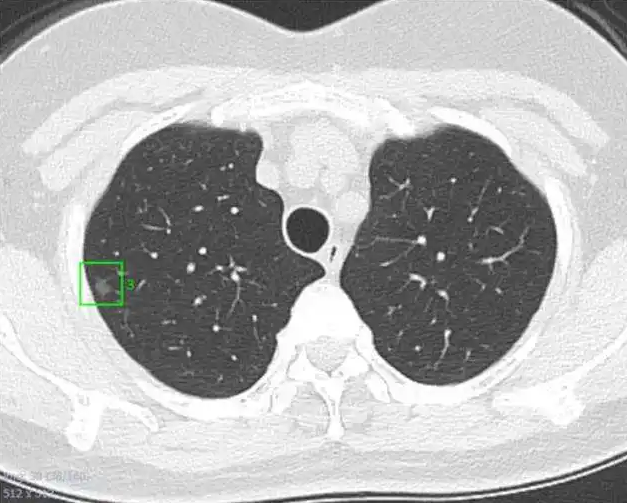

现在体检查出肺部结节的人们越来越多,很多人认为查出肺结节就意味着自己得了肺癌,搞得自己和家人都非常紧张。引起肺部小结节的原因有很多,常见的如炎症肉芽肿、肿瘤、结核或真菌感染等。小结节很难弄清楚它是“好的”、还是“坏的”(如果一发现就贸然手术,切除一叶肺叶至少会损20%的肺功能),所以需要定期复查,它会长大那就是不好的。有些人又会提出疑问,万一是肿瘤,没有及时处理等扩散就啥也来不及了。答案是否定的,因为肿瘤的生长有一定的周期,特别是在结节很小的时候,3-6个月的复查时间可以让医生看到它的变化,但也大不到它能长到足够扩散及转移的地步。

在影像学上把肺部阴影按照直径大小分为肺结节和肺肿块。

肺结节为直径≤3 cm的局灶性、类圆形、密度增高的实性或亚实性肺部阴影,可为孤立性或多发性。

局部病灶直径>3 cm者称为肺肿块,肺癌的可能性相对较大。

【按数量分】 孤立性结节(单个病灶)→ 多发性结节(2个及以上的病灶)【按病灶大小分】 微小结节(直径<5 mm)→ 小结节(直径为5~10mm)【按密度分】 实性肺结节→ 亚实性肺结节(包含纯磨玻璃结节和部分实性磨玻璃结节)

形成肺结节的原因有很多种,常见的有:恶性肿瘤(原发性肺癌、肺转移瘤、类癌)、感染性肉芽肿、良性肿瘤(如错构瘤)、血管性病变和炎性病变等。

所以,发现肺结节不等于就是患上了肺癌。

≤8mm:3、6、12个月后复查,没有变化的随后1年复查1次;>8mm:3个月后复查,持续存在可考虑PET/CT或手术;小结节多数是“好的”,也有一小撮是“坏蛋”,不过通过复查我们完全可以把它揪出来。因为肿瘤的生长是有规律的,实性结节(癌性结节)长大一倍(体积增大一倍与相当于直径增加26%)需要100-400天,亚实性结节需要3-5年。所以,3-6个月的复查时间可以让医生看到它的变化,但也大不到它能长到足够扩散及转移的地步。

所有结节如果随访期间增大或实性成分增多,需手术。